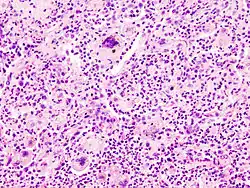

Nekrose

Nekrose ist das intravitale Absterben von Zellen

Mikro: (nach Ablauf der Manifestationszeit!)

- Homogenisierung des Zytoplasmas

- Azidophilie, Eosinophilie

- Kernpyknose, -lyse, -rhexis

- Verlust zellspezifischer Parameter (z.B. Querstreifung beim Herzinfarkt)

- Entzündungsreaktion